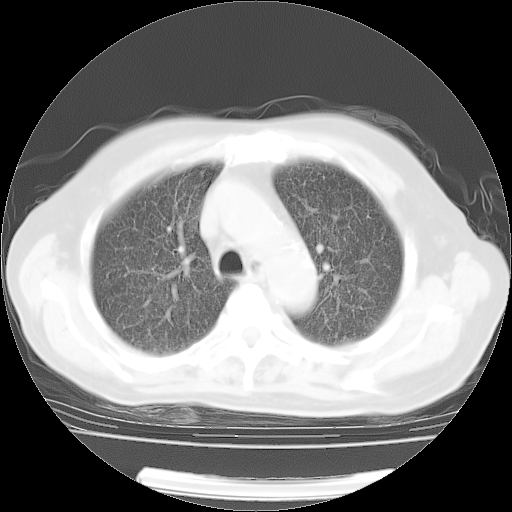

肺部CT平扫未见异常。

4月14日肺部CT